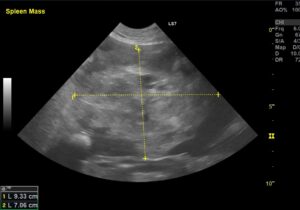

血管肉腫が最もよく発生する部位は脾臓です。

最も多く発生する脾臓、肝臓、心臓(右心房)、その他に皮膚、皮下組織にできることもあります。脾臓に発生する悪性腫瘍の約50%を占めるとも言われています。

食欲不振、腹囲膨満(お腹がぽっこり膨れて見えること)の症状がみられることもありますし、無症状で健康診断時の画像検査でたまたま見つかることもあります。

主に血液検査、レントゲン検査、超音波検査(胸部・腹部)を行います。腫瘍が大きすぎたり、隣接する臓器との関係性がわからない場合はCT検査を行います。

脾臓や肝臓に発生した血管肉腫の場合は外科的に切除する手術が望ましいです。